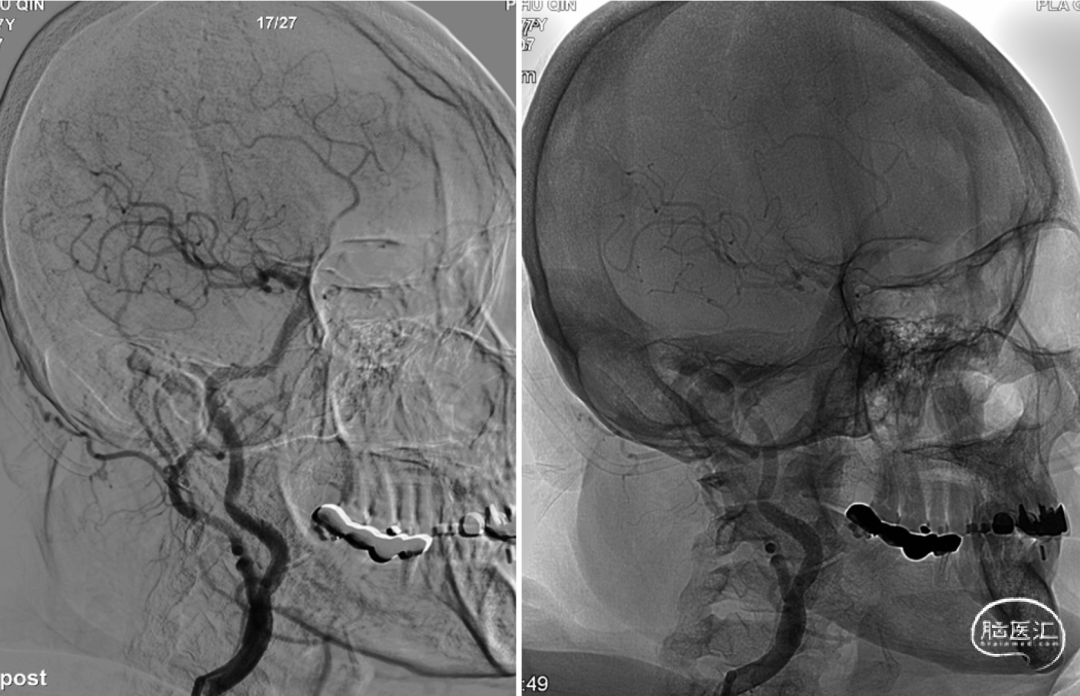

再次使用更大的AVIATOR5*30mm球囊进行支架后扩张,球囊扩张后可见支架残余狭窄解除,再次使用保护伞回收鞘内衬Echelon-10微导管顺利通过支架,成功回收保护伞。造影颈动脉支架植入术后残余轻度狭窄。

图.6 术后侧位造影